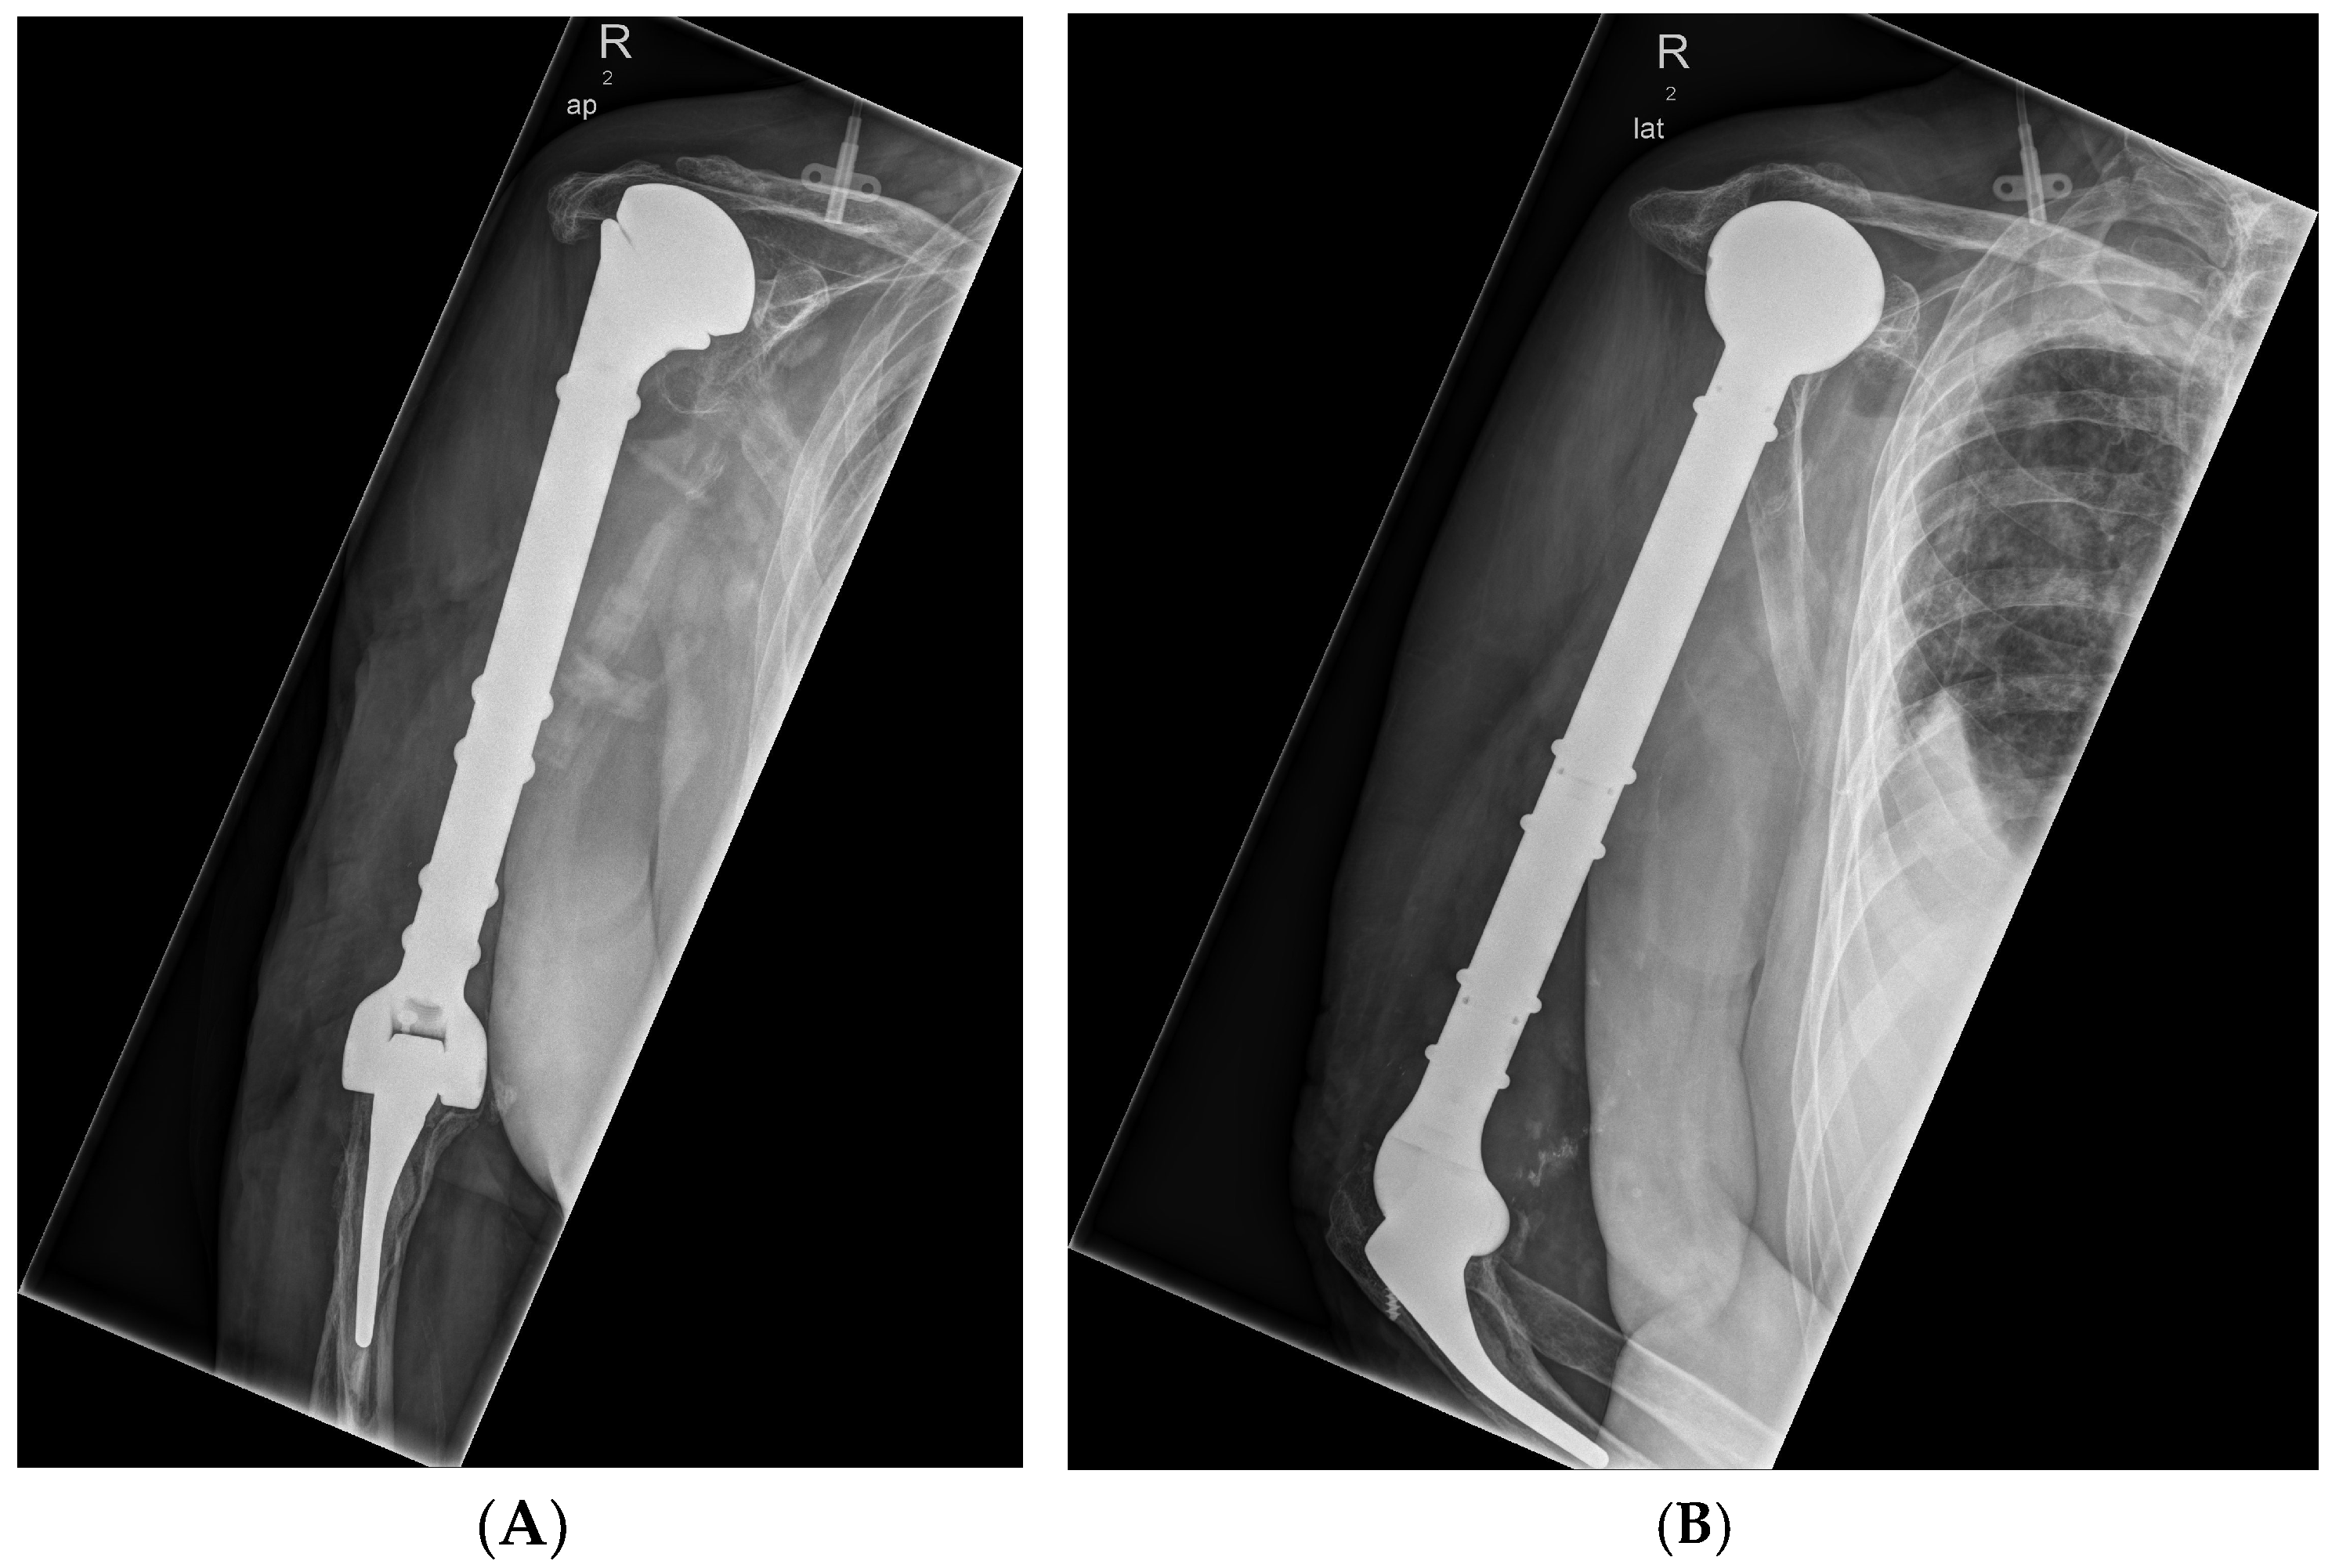

3.2.2. Case 2—Humerus

- ▪ Chronic periprosthetic infection of the implanted alloplastic humerus and elbow joint replacement on the right side with fistula

- ▪ Infection-related loosening of a modular elbow joint endoprosthesis with osteitis of the proximal humerus on the right side